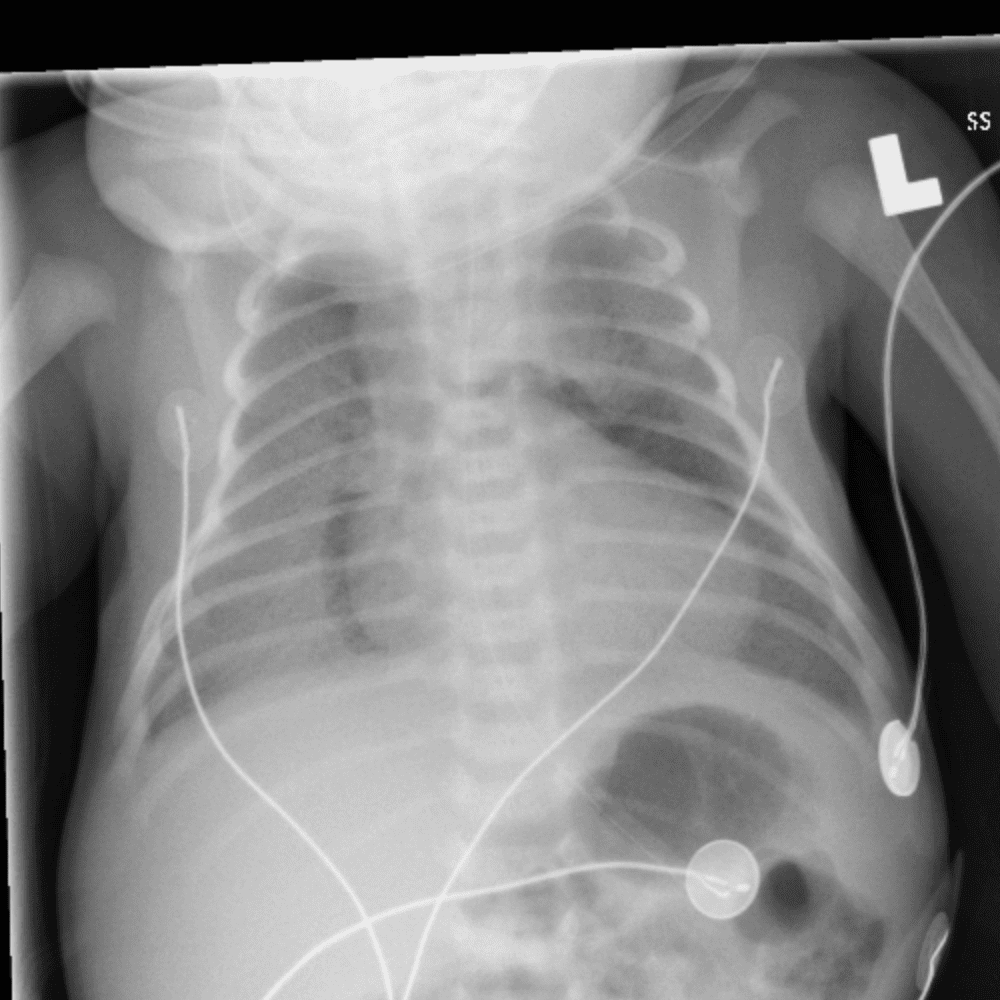

Peds Chest

Practice

Simulates call by including subtle or difficult cases and some normals.

50 cases